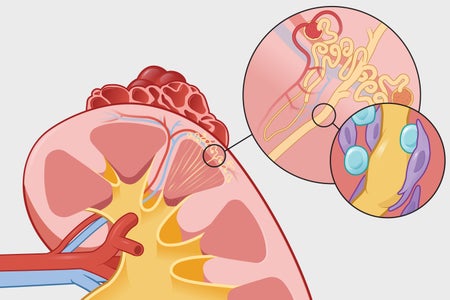

The number of kidney patients is going up

Chronic kidney disease has a variety of causes, ranging from immune system problems to medication side effects

The number of kidney patients is going up

Chronic kidney disease has a variety of causes, ranging from immune system problems to medication side effects